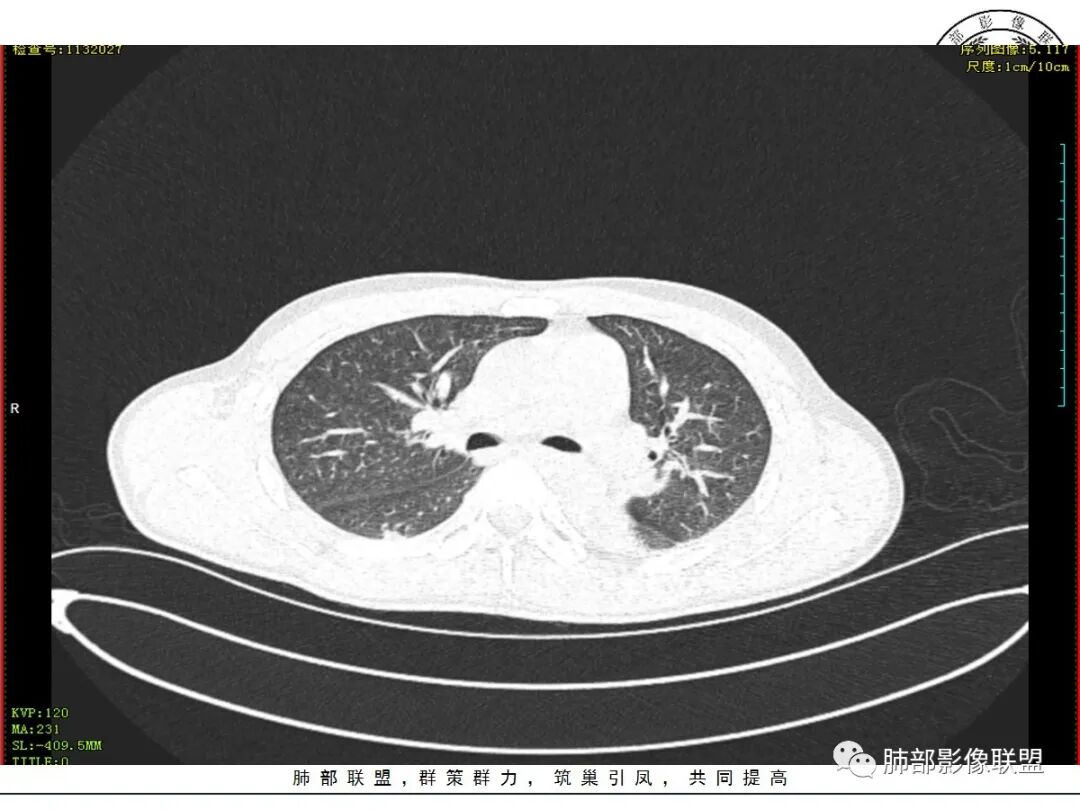

青年男性患者,气促7小时入院,白细胞及中性粒明显增高,PCT增高,CRP不高,心率快,呼吸急促,意识模糊,低氧血症,I型呼吸衰竭,PH偏低,失代偿性酸中毒,BNP偏高,胸部CT:双肺弥漫性多发斑片状实变密度影,双上肺明显,间质改变为主,综合:年轻男性,急性起病,迅速恶化,考虑中毒可能,鉴别:PCP,过敏,

双肺上叶,下叶背段多发斑片状实变影,以胸膜下分布为主,部分重力作用,以背侧为主,部分小叶间质增厚,部分周围伴有散在磨玻璃影,边界欠清,临床急性病程,血象增及PCT明显增高,意识模糊,考虑:吸入性肺炎?鉴别:AHP?CEP?PCP

37岁男性 气促 两肺对称分布磨玻璃及小叶间隔增厚,两肺上叶后段及下叶背段为著,有重力分布,下部密度较高,请结合病史排查肺水肿,理化性肺泡损伤

双肺叶透亮度对称性减低,呈磨砂状,小叶间隔规则增厚,上叶为甚,左右肺叶中轴间质增厚(示淋巴回流障碍),双肺叶弥散磨GGO征,以肺腺泡分布,双肺上,下叶融合片状,有重力分布特点,心脏大,肺动脉干增粗,首选心源性肺水肿,但无胸腔积液。与急性肺损伤和ARDS鉴别

影像:两肺上叶小叶间隔增厚,斑片,腺泡结节,重力分布,下肺不累及

青年男性,气促7小时入院,意识模糊,白细胞及中性粒明显增高,PCT增高,CRP不高,心率快,体温正常,血压正常。胸部CT:双肺上叶小叶间隔光滑增厚,中轴间质增厚,弥漫性磨玻璃、多发斑片影,以上肺、背侧分布为主。影像表现考虑为肺水肿。病因:病史不支持肾功能衰竭、心源性、高原性肺水肿,无发热,似乎也不支持细菌、病毒、真菌等感染引起。吸入毒物?吸入水?

对称性小叶间隔增厚

高密度影重力趋势

病灶的分布以上肺为主

确实要考虑吸入,倾向于吸入的是气体类的可能,因为朝上走

结合病史,最终诊断是 “急性烟雾吸入性肺损伤”,影像学表现主要是肺水肿及弥漫性肺泡损伤改变,因为烟雾气体吸入肺内分布以上肺显著,因此影像学表现也是累及上肺更明显。损伤因素包括大量一氧化碳 二氧化碳 一氧化氮等燃烧产生的有毒气体,也有烟雾粉尘颗粒对气道黏膜的损伤。